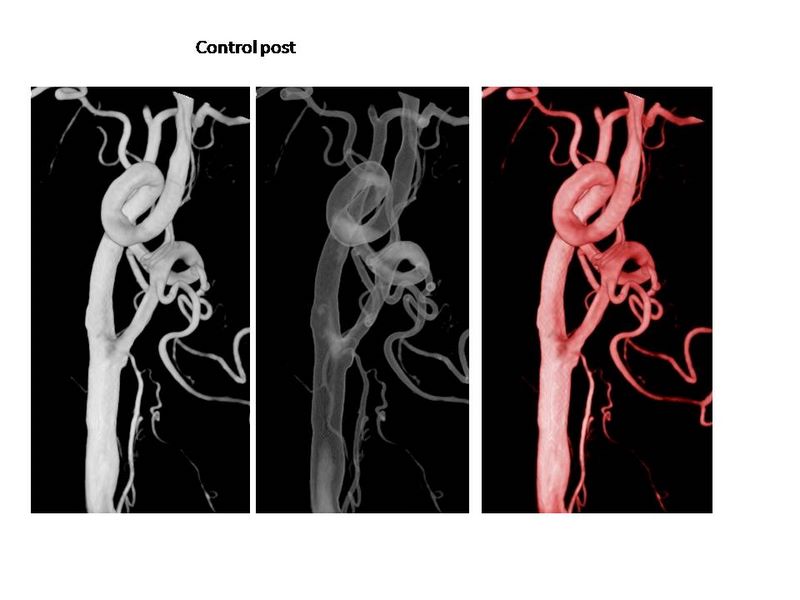

Otro Stent Carotideo